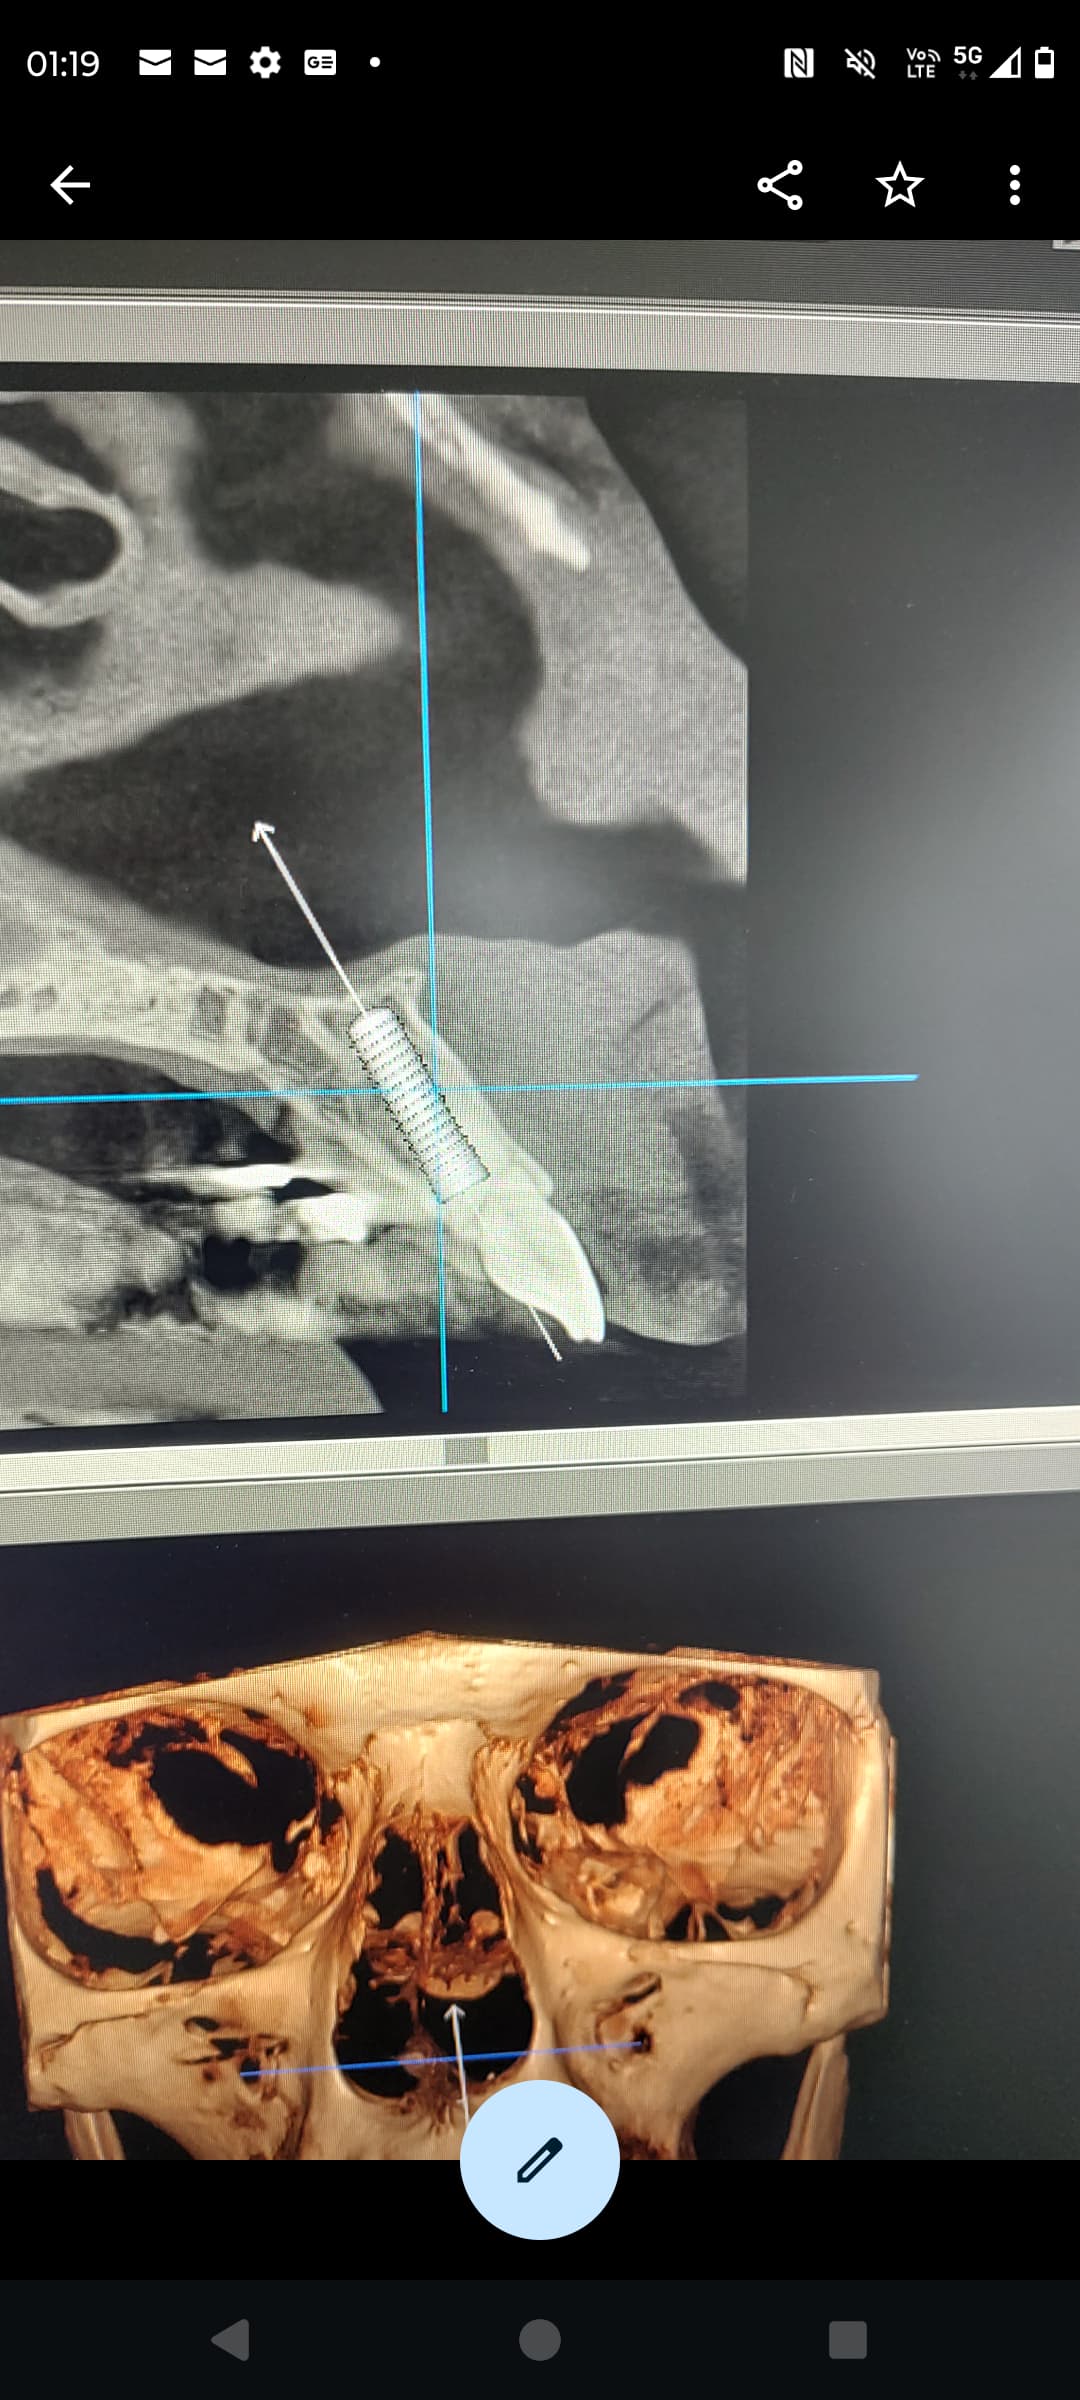

Yes, it was fully digital, but trying to gain more stabilite, i Have drilled longer than the planning, thats why its a bit deeper than i whant.

im confused. how you know your implant is 3mm from the buccal plate. the sagittal view you provided is a planned implant position not the actual CT scan of post implant placement. from your PA. the implant seems more than 5mm from the gingival margin. more like 8mm.